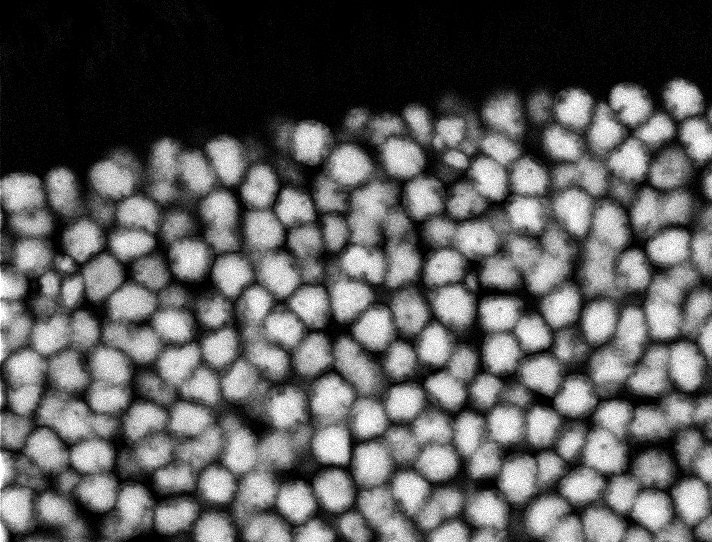

Overview 2

Actin

Nuclei

Nuclei - Bip

Tubulin